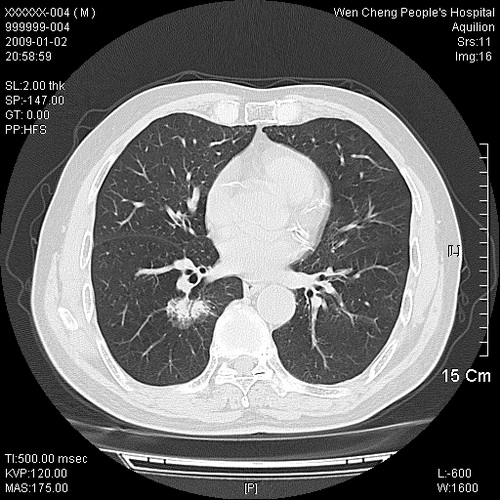

男性,73岁,有慢支病史,肿瘤系列标志物检验正常,血沉及血常规正常

右肺下叶背段小片状 磨玻璃样模糊影,内见血管及含气支气管像,支气管管壁增厚。考虑:慢性炎症!

右肺下叶背段小片状 实性与磨玻璃样影,内见血管及含气支气管像,支气管管壁增厚,边缘见长毛刺影。考虑:慢性炎症或肿瘤!建议抗炎治疗复查,密切观察随访!

右肺下叶片团状影内见扩张的含气支气管和支气管管壁增厚,其周有磨玻璃样模糊影和长毛刺。考虑慢性炎症可能性大。

2、右肺下叶片团状影内见扩张的含气支气管和支气管管壁增厚,其周有磨玻璃样模糊影和长毛刺。考虑周围型肺ca可能,结核不排。

高度提示细支气管肺泡癌,建议抗炎治疗半月观察病灶变化,如无明显改变,建议立即手术治疗.

病变形态非常不好呀,临床上血常规及症状也不明显,不太支持炎性病灶,高度警惕肿瘤病变,最好做个纤支镜检查。